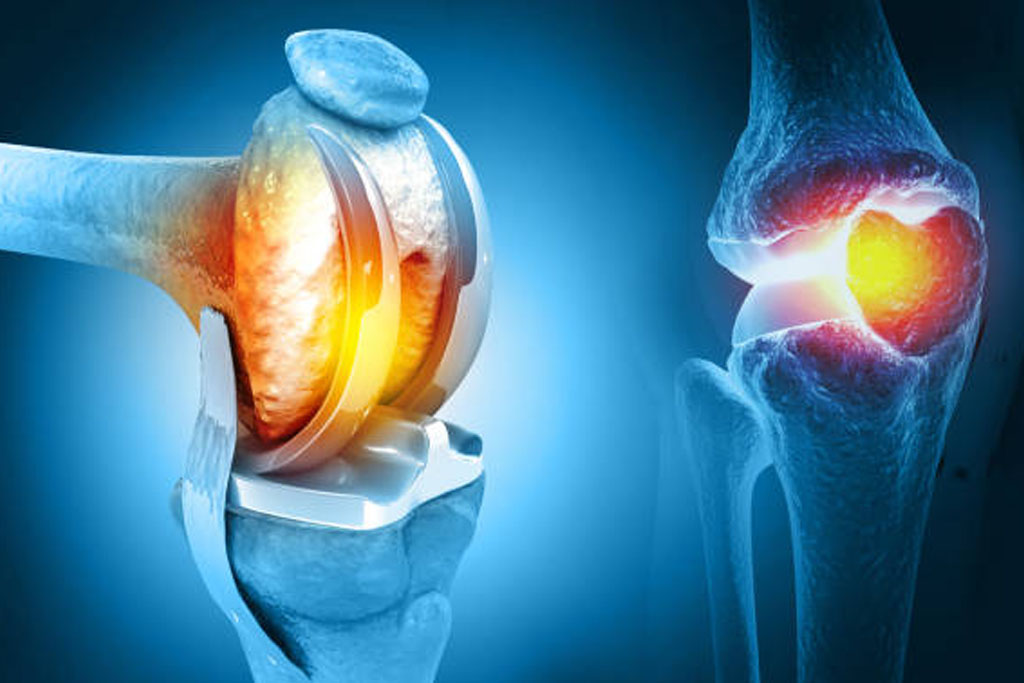

Joint Replacement Surgery